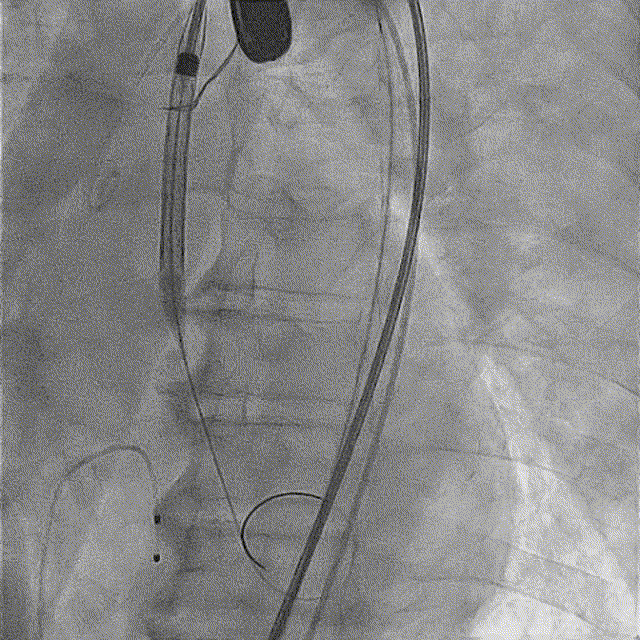

TaurusNXT植入过程

全麻后超声引导下建立入路,左侧股动脉置入TaurusNavi 20F血管鞘。跨瓣后左室放置Lunderquist导丝,使用TaurusAtlas 20mm球囊预扩,球囊无明显位移,有轻微腰征、无漏。输送系统预备同侧Snare从右股动脉送入,安全顺利通过主动脉弓。瓣膜在双窦展开位约瓣上2mm位初始定位释放,工作位造影多角度评估后予以释放(一次定位释放,未采用多次回收功能)。超声下显示瓣膜偏椭圆,之后使用TaurusAtlas 22mm球囊后扩,支架形态改善明显,导管测压由术前的70mmHg即刻下降至1mmHg,术后即刻超声心动图评估显示瓣膜位置良好,微量瓣周漏,血流动力学指标理想。

术中影像

主动脉根部造影

球囊预扩

预备Snare跨瓣

瓣膜初始定位

工作位造影(双窦展开位)

完全释放

球囊后扩

最终造影